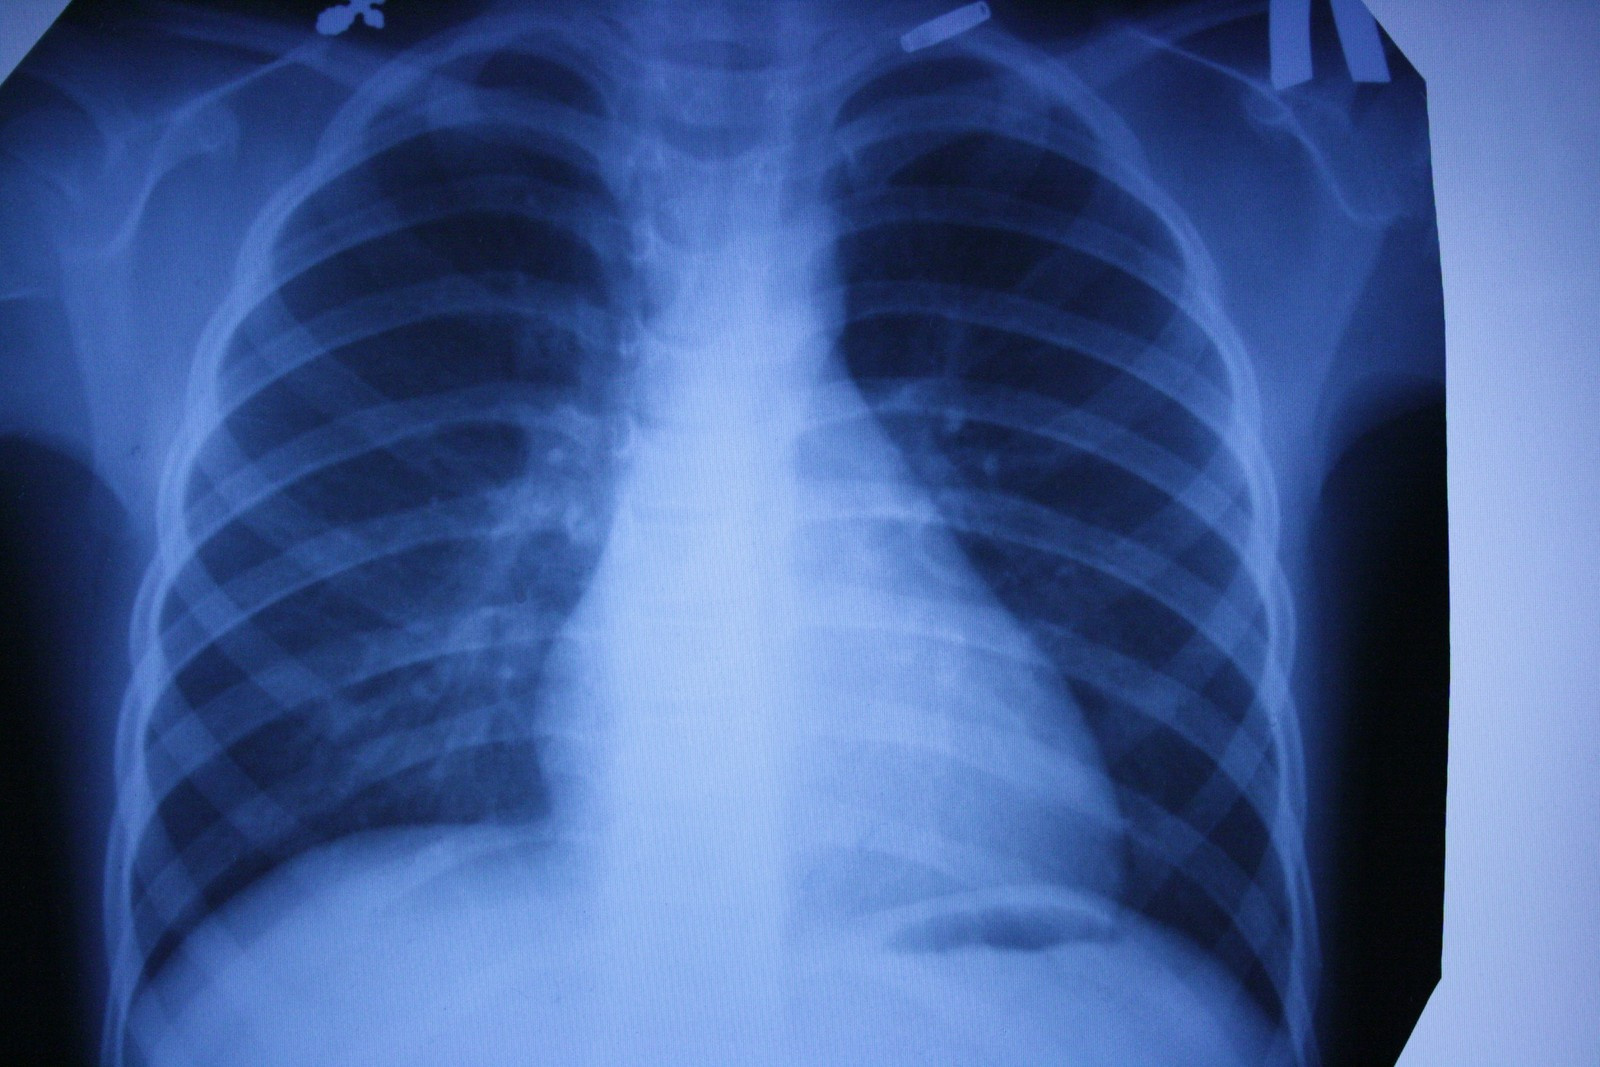

Рентгеновские снимки — первая в мире диагностическая визуализация. Сложно представить современную больницу без такого обследования. Это и флюорография для проверки наших легких, и снимки при заболеваниях суставов или переломах костей. Обнаружение на ранних стадиях туберкулеза или опухоли в легких увеличивает шансы на выздоровление. Кроме того, жесткое рентгеновское излучение может уничтожать раковые клетки. Принципы современной рентгеноскопии используются и в системах безопасности (сканеры в аэропортах, вокзалах и т. д.), и в производстве. В металлургии или машиностроении равномерность просканированной X-лучами структуры указывает на хорошие прочностные характеристики деталей. Таким же образом проверяются прочность бетонных конструкций для монолитного домостроения, сварные швы сложных металлоконструкций.

Продолжая изучать X-лучи, Рентген получил на своем оборудовании первый снимок костного скелета — кисти руки. С тех пор основные элементы обычного рентгеновского аппарата мало изменились: катодная (рентгеновская) трубка, питающее устройство (два трансформатора) и пленка-фотобумага из соединений серебра с галогенами, которые темнеют с различной интенсивностью в зависимости от плотности просвечиваемого материала и тем самым формируют изображение.